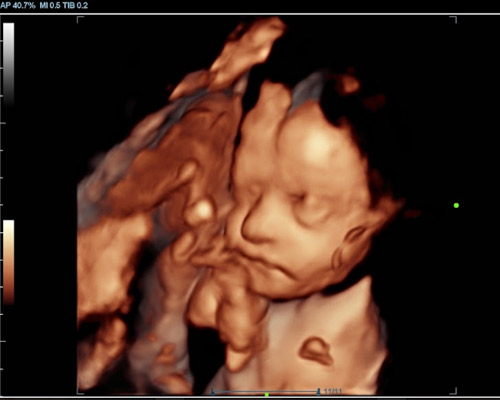

A 3D scan produces detailed still images that show the baby’s face and body in three dimensions. A 4D baby scan near Nottingham goes a step further by displaying those images in motion, allowing parents to see their baby move, stretch, or even smile.

During a 4D baby scan near Nottingham, HD Live technology creates images that appear more natural by adding light and shadow effects. This results in clearer, more lifelike visuals than traditional ultrasound images.

- Highly Detailed Images - Parents can see facial features more clearly during a 4D bonding scan.